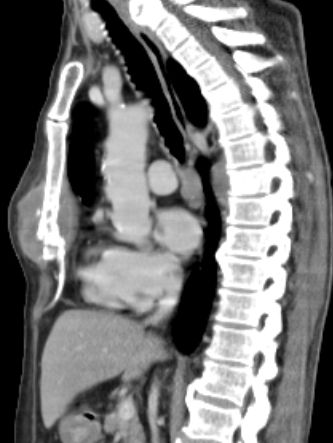

66-jähriger Patient mit einer Stenose des distalen Ösophagus. Histologisch invasives Adenokarzinom.![]() |

![]() |

Im 9. Brustwirbelkörper eine lytische Knochenmetastase.![]() |